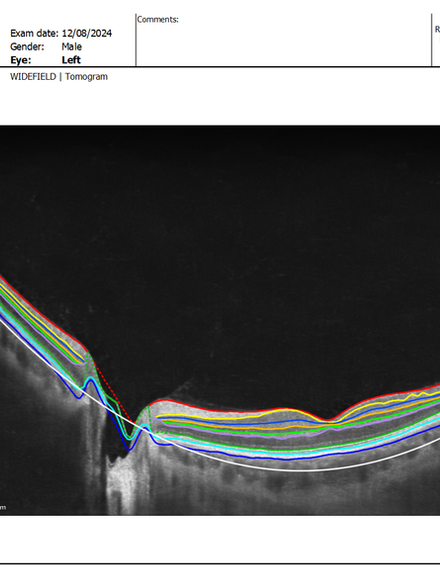

Avaliação dos Olhos

Avalia-se o olho e o paciente para indicar a cirurgia e a melhor lente intraocular:

-Córnea (formato, curvatura).

-Retina e Mácula (saúde).

-Nervo Óptico (risco de glaucoma)

Exames Realizados Na Avaliação de Catarata na Ortolan Oftalmologia